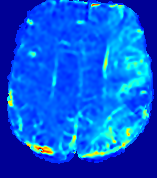

4.3.1 Advection Imaging via Advection-Diffusion

Slice #1Slice #2Slice #3Slice #4Slice #5Slice #6𝐕gt𝟐subscriptnormsuperscript𝐕gt2\|\bf{V}^{\text{gt}}\|_{2}Refer to captionRefer to captionRefer to captionRefer to captionRefer to captionRefer to caption𝐕est𝟐subscriptnormsuperscript𝐕est2\|\bf{V}^{\text{est}}\|_{2}Refer to captionRefer to captionRefer to captionRefer to captionRefer to captionRefer to captionRefer to caption1.51.51.51.21.21.20.90.90.90.60.60.60.30.30.30.00.00.0(mm/s)𝑚𝑚𝑠(mm/s)Destsuperscript𝐷estD^{\text{est}}Refer to captionRefer to captionRefer to captionRefer to captionRefer to captionRefer to captionRefer to caption0.0150.0150.0150.0120.0120.0120.0090.0090.0090.0060.0060.0060.0030.0030.0030.0000.0000.000(mm2/s)𝑚superscript𝑚2𝑠(mm^{2}/s)

Figure 14: PIANO identifiability testing: advection imaging via advection-diffusion. Top row shows 𝐕gt2subscriptnormsuperscript𝐕gt2\|{\bf{V}}^{\text{gt}}\|_{2} used for simulating ground truth pure advection. Rows below show the estimated 𝐕est2subscriptnormsuperscript𝐕est2\|{\bf{V}}^{\text{est}}\|_{2} and Destsuperscript𝐷estD^{\text{est}} on corresponding slices. Note that the plotted value scale for Destsuperscript𝐷estD^{\text{est}} is 0.01 of that for 𝐕gt2subscriptnormsuperscript𝐕gt2\|{\bf{V}}^{\text{gt}}\|_{2} and 𝐕est2subscriptnormsuperscript𝐕est2\|{\bf{V}}^{\text{est}}\|_{2}.

We use the same ‘Advection Imaging’ simulation of Sec. 4.2.1 as the concentration dataset for PIANO. However, instead of modeling pure advection (Eq. 15), we let PIANO estimate both velocity 𝐕estsuperscript𝐕est{\bf{V}}^{\text{est}} and diffusivity Destsuperscript𝐷estD^{\text{est}} via the advection-diffusion PDE (Eq. 2) underlying the proposed PIANO model. Fig. 14 shows the estimated 𝐕est2,subscriptnormsuperscript𝐕est2\|{\bf{V}}^{\text{est}}\|_{2}, and Destsuperscript𝐷estD^{\text{est}} fields for one patient. Although PIANO has the freedom to estimate both a velocity and a diffusivity field from pure advection, PIANO differentiates well between advection and diffusion: the estimated 𝐕est2subscriptnormsuperscript𝐕est2\|{\bf{V}}^{\text{est}}\|_{2} successfully reproduces the ground truth 𝐕gt2subscriptnormsuperscript𝐕gt2\|{\bf{V}}^{\text{gt}}\|_{2} governing the simulated advection process, just as it already did in the ‘Advection Imaging via Advection’ test (Fig. 12). More importantly, the estimated diffusivity Destsuperscript𝐷estD^{\text{est}} is orders of magnitudes smaller than 𝐕est2subscriptnormsuperscript𝐕est2\|{\bf{V}}^{\text{est}}\|_{2}, indicating the estimated diffusion is negligible compared to the estimated advection, which is highly consistent with the underlying pure advection of the simulated data.